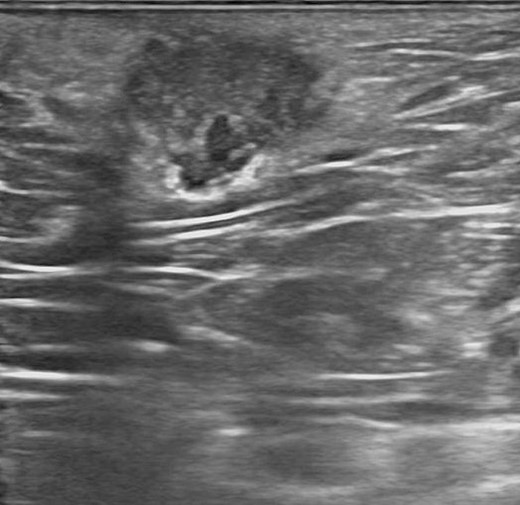

Physical examination showed 1.5 cm size hard tender swelling at perianal area at 11 o’clock position. Episiotomy scar was showed at the lateral side of the swelling. Laboratory tests including complete blood count, inflammatory markers were within normal limits. Viral markers for hepatitis B and serologic studies of an immunocompromised state were all negative. Anoscopic exam showed mild internal hemorrhoids with normal rectal mucosa. Endoanal ultrasound showed normal findings with no evidence of abscess or fistula. Transperineal ultrasound showed a 1.5 cm size irregular mixed echogenicity lesion without involving anal sphincters (Fig. 1). The patient underwent wide excision under local anesthesia. The incision was made with the previous episiotomy scar. 1.5 cm size fibrotic whitish mass with chocolate brown color spots was obtained. Histopathological examination showed several irregular dilated endometrial glands along with stroma in perineal tissue, confirmed as endometriosis (Fig. 2). The postoperative course was uneventful. She had no evidence of recurrence of 6 months follow up.

Transperineal ultrasound showed a 1.5 cm size irregular mixed echogenicity lesion.